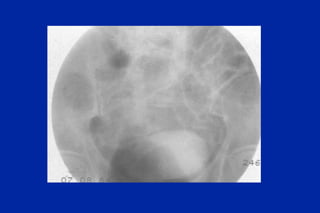

Este documento resume los principales tipos y técnicas de angiografía. Describe brevemente la angiografía, arteriografía, flebografía y linfografía, así como las técnicas de contraste y materiales utilizados. También explica los principales accesos vasculares, la técnica de Seldinger, la angiografía por sustracción digital y algunas técnicas endovasculares comunes.